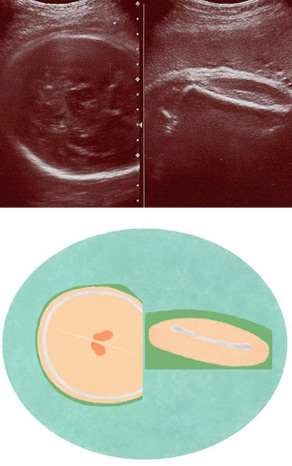

妊娠37週ころの超音波写真

髪の毛や産毛は生えていても写りません

頭の中の大脳は白子のように詰まって見えます。髪の毛や産毛は生えていても写りません。大腿骨(太ももの骨)が白くはっきり写っています。